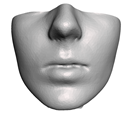

2.6. Textured Output Visualization